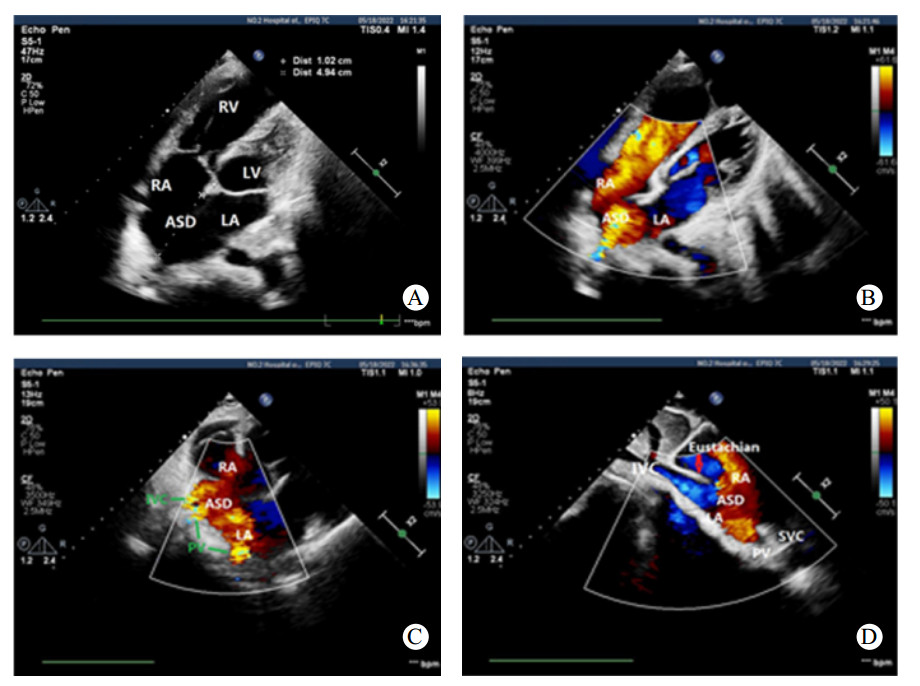

1 资料与方法患者,男性,21岁,于2022年5月18日收治本院,无明显不适主诉,15年前体检时发现ASD,长期门诊随访。患者近期门诊随访时外院心脏超声提示:房间隔缺损(继发孔型),右心增大,肺动脉增宽,轻度肺动脉高压(肺动脉平均压33 mmHg,1 mmHg=0.133 kPa),考虑患者房间隔缺损,存在手术指征,建议手术治疗,门诊以“房间隔缺损”收住入院。入院时查体:神志清楚,体温: 37.2℃,脉搏: 73次/min,血压: 109/66 mmHg,口唇无发绀,可见杵状指,颈静脉无怒张,双肺呼吸音清,未闻及明显干湿啰音,心律不齐,肺动脉瓣听诊区可闻及收缩期杂音,腹软,无压痛及反跳痛,肝脾肋下未及,双侧肾区无明显叩痛,脊柱侧弯,双下肢无水肿,神经系统检查阴性。血气分析氧分压:57 mmHg,血氧饱和度:88.7%,血、尿常规、生化、凝血项无殊。本院经胸心脏超声提示:先天性心脏病, 巨大房间隔缺损合并下腔静脉回流入左房(右向左分流),右心增大,轻度肺动脉高压,估测肺动脉收缩压(pulmonary artery systolic pressure,PASP)40 mmHg(图 1)。胸部高分辨CT平扫提示:心脏饱满,提示肺静脉异常引流,房间隔缺损可能,建议增强(图 2)。术前诊断:先天性心脏病:巨大房间隔缺损(下腔静脉侧及房顶部无房间隔残留组织),轻度肺动脉高压,完全性右束支传导阻滞,脊柱侧弯,胆囊内息肉。根据术前检查,决定进行心脏不停跳房缺修补术(人造补片)以及三尖瓣成形术。全麻后,沿胸骨正中切口开胸,切开右心房,术中所见:右心明显增大,房间隔缺损,下腔静脉无残端,大小约4.0 cm×5.0 cm,三尖瓣瓣环增大,约43 mm, 少量反流,未见肺静脉异位引流、室间隔缺损、动脉导管未闭、下腔静脉异位引流等心内其他畸形。手术体外循环下不停跳牛心包补片修补房缺,三尖瓣成形、置入28# SORIN成形环一枚(图 3)。术程顺利,术后即刻经食道超声未见房间隔明显残余分流,三尖瓣未见明显反流。心电图示窦性心律。术后给与头孢呋辛钠预防感染,护胃、化痰、利尿等对症支持治疗。术后经胸心脏超声提示:房间隔缺损修补术后,房水平未见残余分流,三尖瓣成形术后(图 4)。手术前后左心功能未见明显异常(表 1)。经1周治疗后,患者恢复良好,血气分析氧分压:141 mmHg,血氧饱和度:99.9%,予带药出院。

| A: 胸骨旁四腔心切面显示房间隔回声失落(房顶部无残余房间隔组织);B、C: 彩色多普勒显示左房和右房间存在过隔血流;D:剑下两腔心切面显示下腔静脉血流在欧氏瓣的引导下回流入左房。LA: 左房;RA: 右房;LV: 左室;RV:右室;ASD:房间隔缺损;IVC: 下腔静脉;SVC: 上腔静脉;PV: 肺静脉;Eustachian:欧式瓣 图 1 患者术前经胸心脏超声表现 |